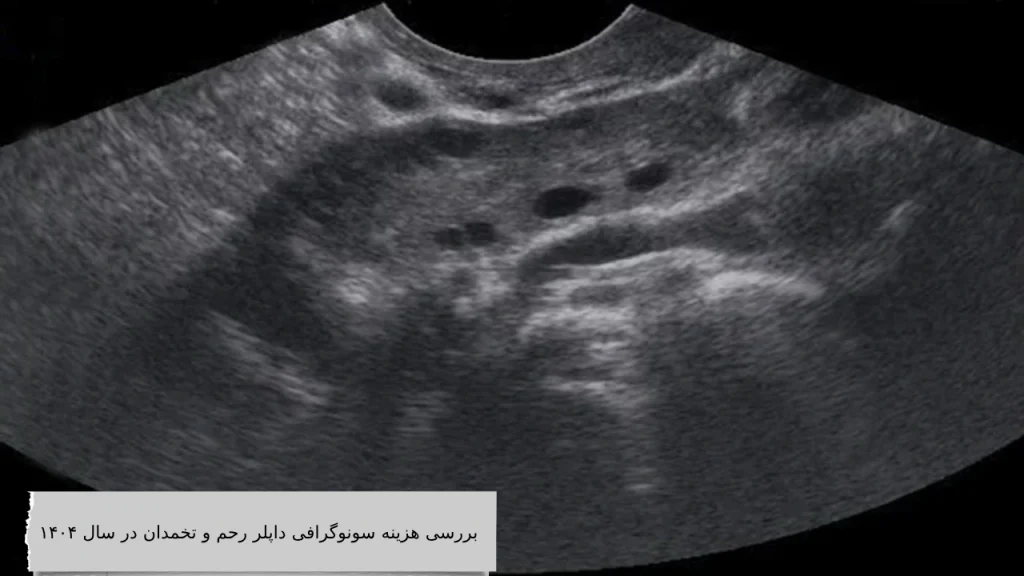

بررسی هزینه سونوگرافی داپلر رحم و تخمدان در سال ۱۴۰۵

در سال ۱۴۰۵، هزینه سونوگرافی داپلر رحم و تخمدان در ایران بسته به نوع مرکز، تخصص پزشک، و پوشش بیمهای، بین ۳۰۰ هزار تا ۷۰۰ هزار تومان در نوسان است. در برخی مراکز تصویربرداری پیشرفته یا کلینیکهای خصوصی در شهرهای بزرگ، این مبلغ ممکن است به حدود یک میلیون تومان هم برسد. با این حال، در مراکز دولتی یا تحت پوشش بیمههای پایه، هزینه سونوگرافی داپلر رحم و تخمدان ممکن است به شکل قابلتوجهی کاهش یابد. این بازه قیمتی نسبت به سال گذشته افزایش اندکی داشته که عمدتاً به دلیل تغییرات اقتصادی، تورم و بهروزرسانی تعرفههای پزشکی است.

در شهرهایی مانند تهران، مشهد، شیراز، تبریز و اصفهان که خدمات پزشکی پیشرفتهتری ارائه میشود، هزینه سونوگرافی داپلر رحم و تخمدان معمولاً بالاتر است. در مقابل، در بسیاری از شهرستانها بهویژه در مراکز دولتی، قیمتها مقرونبهصرفهتر هستند. بهعنوان نمونه، یک سونوگرافی داپلر در شمال تهران ممکن است ۹۰۰ هزار تومان هزینه داشته باشد، در حالی که همان خدمت در یک مرکز دولتی در یزد یا کرمان ممکن است با حدود ۳۵۰ هزار تومان انجام شود.